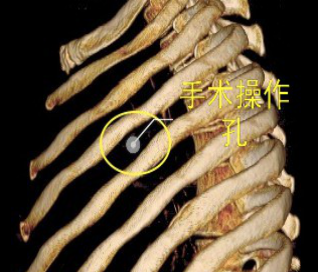

较两孔、多孔胸腔镜手术或传统手术,单孔手术具有创伤更小、出血更少、术后疼痛更轻、瘢痕小、切口更加美观、术后恢复快、住院时间短等优势。但手术中所有器械(包括观察镜、吸引器、电凝钩、切割闭合器、双关节等各种操作器械)都要是从一个小“孔”进入,器械之间的互相干扰,同时器械与观察镜几乎平行,视野非常狭窄,手术难度明显,增加极其考验医生的技术。

器械进入小孔。